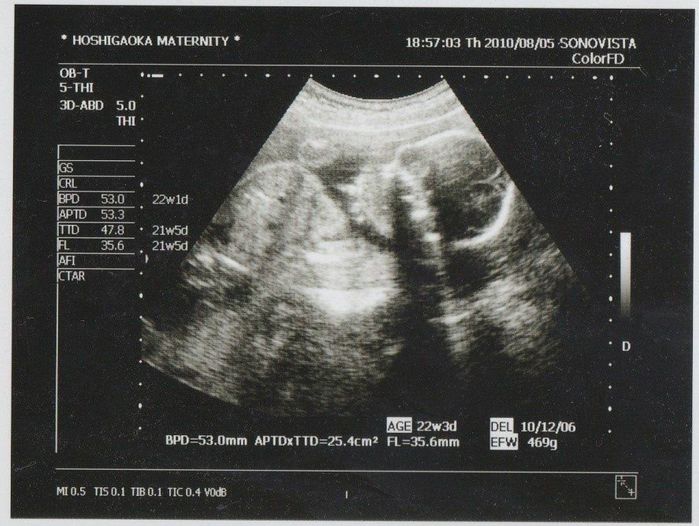

妊娠21週目のエコー写真

推定体重469g。右上に頭、左側に体、左上の丸いのは手のように見えます。この頃からおなかの中で空気がポコポコするような胎動が感じ始められました。この健診の次の週から2週間程カナダへ旅行しました。妊娠中の長期海外旅行に不安もありましたが、体調もよく妊娠も順調だったので、夫と二人で最後の旅行を楽しむことにしました。